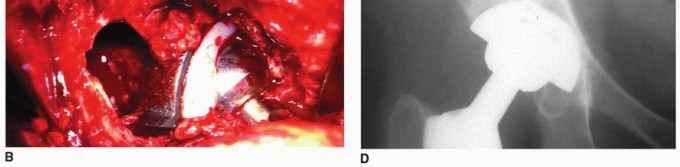

هشاشة العظام حول مفصل الورك الاصطناعي هي تآكل عظمي شائع بعد جراحة استبدال مفصل الورك الكلي، غالبًا بسبب جزيئات البولي إيثيلين. يبدأ العلاج بالتشخيص الدقيق عبر الأشعة المقطعية، ويُعد تبديل بطانة البولي إيثيلين حلاً فعالاً للمكونات الثابتة، مما يقلل الألم ويستعيد وظيفة المفصل بفضل خبرة الأستاذ الدكتور محمد هطيف.

الخلاصة الطبية السريعة: هشاشة العظام حول مفصل الورك الاصطناعي هي تآكل عظمي شائع بعد جراحة استبدال مفصل الورك الكلي، غالبًا بسبب جزيئات البولي إيثيلين. يبدأ العلاج بالتشخيص الدقيق عبر الأشعة المقطعية، ويُعد تبديل بطانة البولي إيثيلين حلاً فعالاً للمكونات الثابتة، مما يقلل الألم ويستعيد وظيفة المفصل بفضل خبرة الأستاذ الدكتور محمد هطيف.

يتناول هذا المقال الأسباب والتشخيص وخيارات العلاج لهشاشة العظام التي تحدث حول مكونات الحُق الثابتة ![توضيح طبي: هشاشة العظام حول مفصل الورك الاصطناعي تبديل بطانة البولي إيثيلين الحل الأمثل](/media/upload/ad023e43-fc70-4c74-a667-a1eb6d8e107d.jpg) ![توضيح طبي: هشاشة العظام حول مفصل الورك الاصطناعي تبديل بطانة البولي إيثيلين الحل الأمثل](/media/upload/e718bae5-3e04-4049-b408-451d4ebed9ed.jpg) ![توضيح طبي: هشاشة العظام حول مفصل الورك الاصطناعي تبديل بطانة البولي إيثيلين الحل الأمثل](/media/upload/436dcac0-c732-444a-8403-539f5c46ae88.jpg) ![توضيح طبي: هشاشة العظام حول مفصل الورك الاصطناعي تبديل بطانة البولي إيثيلين الحل الأمثل](/media/upload/5295a9df-4504-4c8c-89b3-71233cb41476.jpg) ![توضيح طبي: هشاشة العظام حول مفصل الورك الاصطناعي تبديل بطانة البولي إيثيلين الحل الأمثل](/media/upload/c2411af8-be23-4562-90d6-94b6e9d0c0d9.jpg) ![توضيح طبي: هشاشة العظام حول مفصل الورك الاصطناعي تبديل بطانة البولي إيثيلين الحل الأمثل](/media/upload/eda756a8-6677-4b09-b6f5-3619857552e2.jpg) ![توضيح طبي: هشاشة العظام حول مفصل الورك الاصطناعي تبديل بطانة البولي إيثيلين الحل الأمثل](/media/upload/d199b219-f355-4caf-85c3-a764f4913cb3.jpg) ![توضيح طبي: هشاشة العظام حول مفصل الورك الاصطناعي تبديل بطانة البولي إيثيلين الحل الأمثل](/media/upload/ddd6b344-5b51-450e-8239-8e832b923988.jpg) ![توضيح طبي: هشاشة العظام حول مفصل الورك الاصطناعي تبديل بطانة البولي إيثيلين الحل الأمثل](/media/upload/86786efa-0a81-438c-984d-749c462862d5.jpg) ---